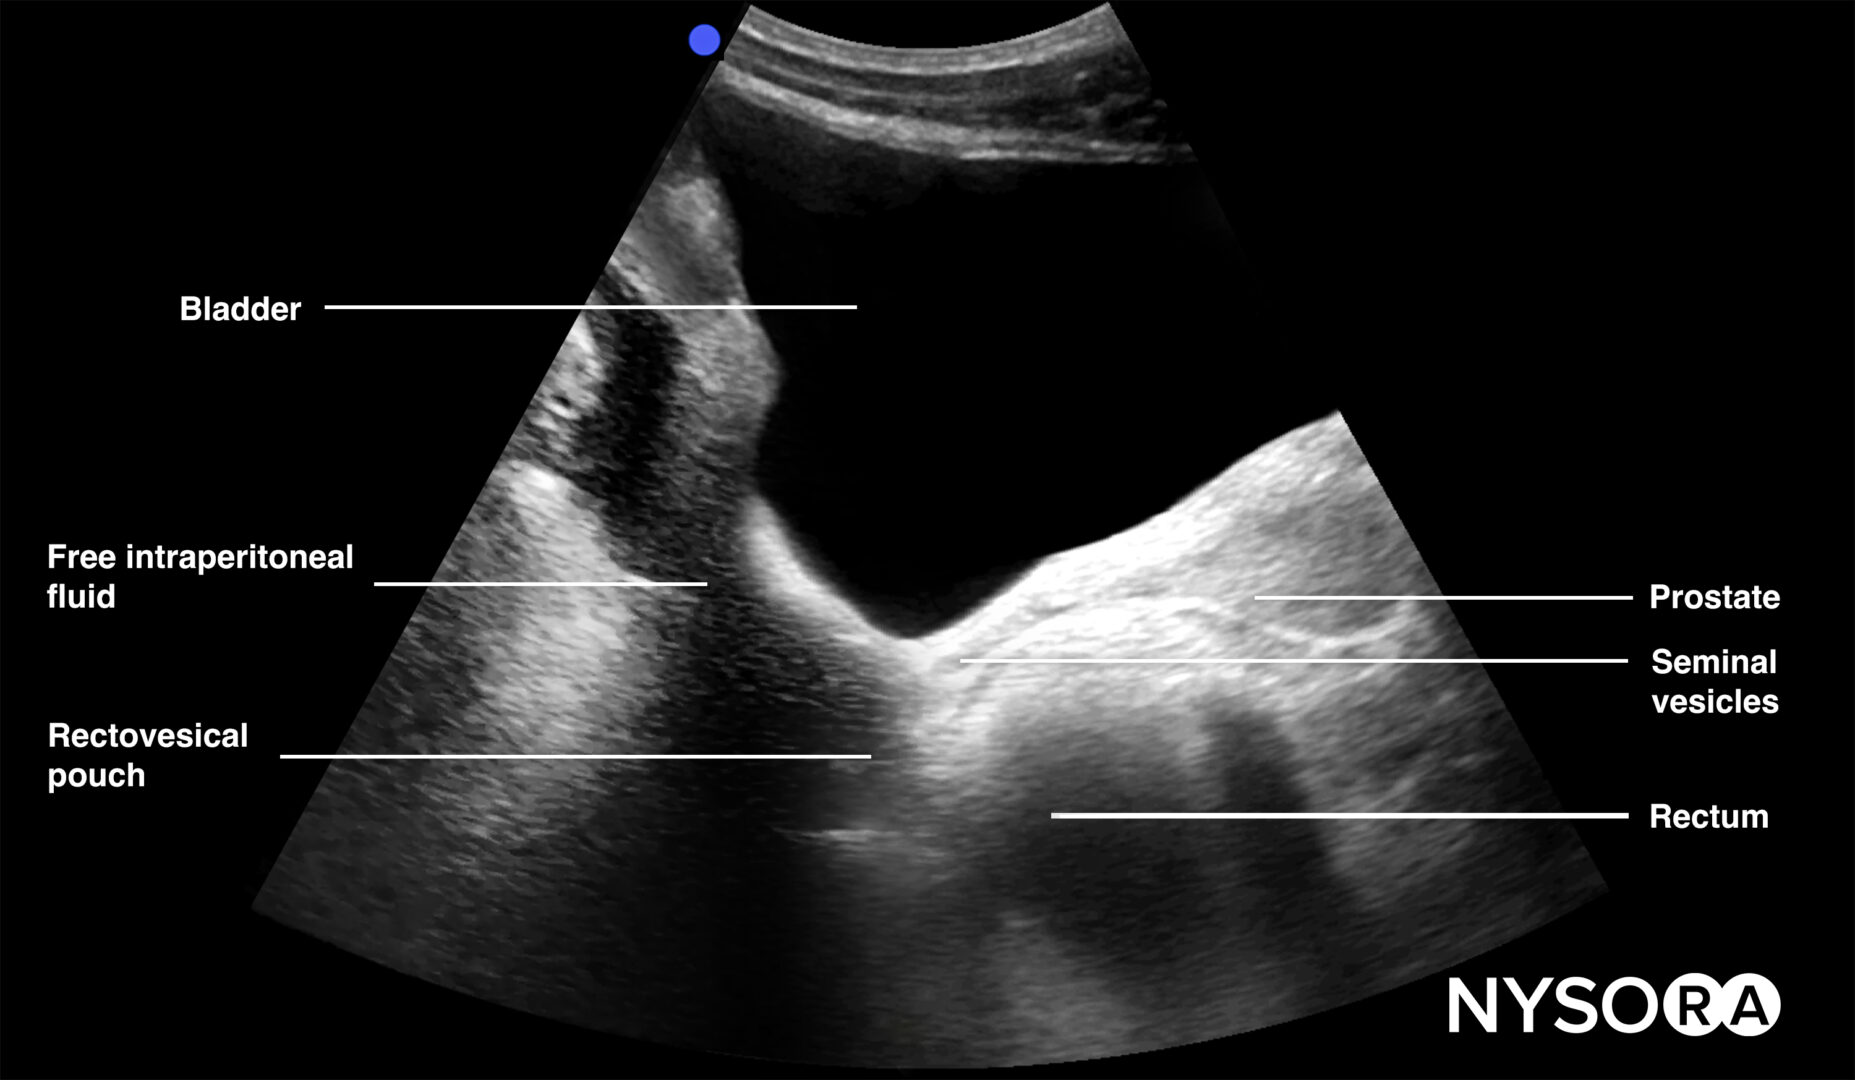

Pelvic free fluid collects behind the bladder or the area lateral to the bladder (rectovesical pouch in men and the rectouterine pouch or pouch of Douglas in women).

Sonoanatomy of interest in males:

Longitudinal view of the male pelvis with free fluid in the rectovesical pouch after Foley catheter insertion.

Tips

- In men, the seminal vesicles may be mistaken for free fluid. However, the vesicles are usually more triangular in shape and symmetrically spaced from the midline in the transverse view.